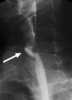

Posttraumatic bladder neck stricture

Bladder outlet obstruction